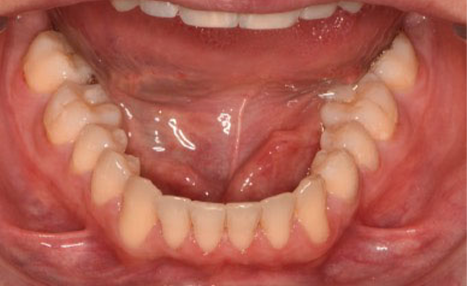

After 16 months of treatment, the transformation was evident:

(Image: 2 years after finishing)